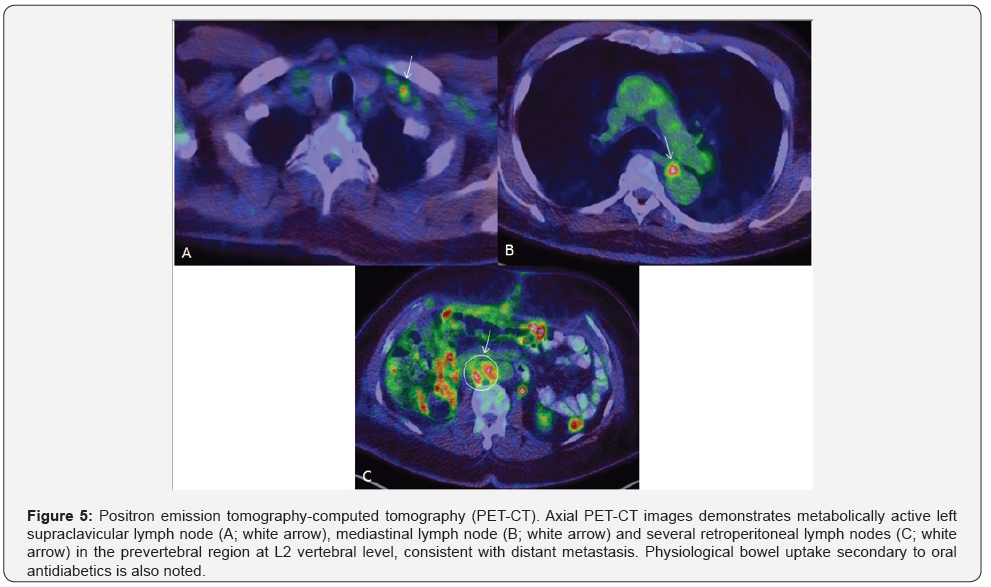

Histopathology demonstrated a uni-focal high-grade papillary urothelial carcinoma containing urothelial cells with large hyperchromatic nuclei, frequent atypical mitotic figures, frank anaplasia and spindle cells representing high-grade sarcomatoid features. The spindle cell component accounted for greater than 60 % of the tumor. Urothelial carcinoma in-situ was also noted. Extensive invasion of the renal parenchyma, renal sinus adipose tissue, renal vein, inferior venal cava and associated lymphovascular invasion by the tumor was seen. No lymph nodes were identified in the surgical specimen. A pathological stage of pT4 pNx was given. The patient had a long intraoperative course followed by SICU admission for gradual weaning from intubation. He was extubated the second day and had an uneventful post-operative recovery. A staging PET CT post-surgery revealed metabolically active metastatic regional retroperitoneal LNs and a solitary mediastinal LN with left supraclavicular LNs suspicious for distant metastasis. Categorically, the malignancy was labeled as a stage IV disease (Figure 5). Radiotherapy was not undertaken for reasons of advanced tumoral stage. The patient was started on carboplatin and gemcitabine for 3 cycles of chemotherapy.